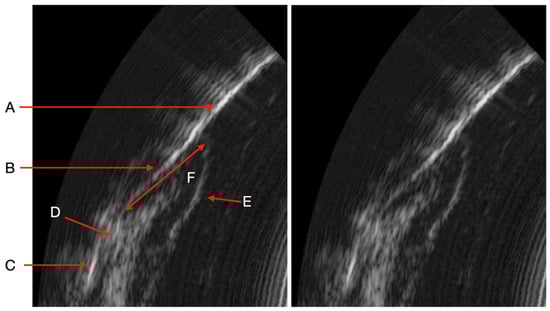

During the study, we observed many variations in ultrasound images depending on the clinical situation (inflammatory area, presence of visible calculus, edema, spontaneous bleeding, normal situation). Indeed, the images can reveal the presence of inflammation in the deep gingival tissues. Sub-gingival calculus can also be visible. The image quality is also different because of the variation in the ultrasound signal [13]. The same is true for subgingival calculus which can also be objectified on the ultrasound images. Although many of these elements appear in the image, AI currently struggles to differentiate pocket depths from surrounding structures in certain clinical contexts. These structures need to be identified and characterized for more precise training of the AI (Figure 4)

Figure 4.

Variations in periodontal ultrasound images. (A) Reference image with normal structures. (B) Presence of deep inflammation with visible connective tissue junction. (C) Presence of deep inflammation without visible connective tissue junction. (D) Presence of supragingival calculus. (E) Presence of subgingival calculus. (F) Presence of calculus above and below the gingival surface and deep inflammation.

It should be noted that we can observe several clinical situations that can give a bias in measuring the periodontal pocket automatically by AI (Figure 2). The detection of significant inflammation in the image can greatly influence the outcome in the difference in pocket depth measurements obtained with the AI algorithm and the manual probe. Indeed, there are situations where the boundary between the inflammation image and the bottom of the pocket is not clear. This is explained by the absence of connective tissue visible on the image. In these specific cases, as it is trained today, the AI algorithm measures the depth of the periodontal pocket associated with the amount of inflammation. In other situations, the boundary is clearly visible on the image and the distinction between the periodontal pocket and the inflammation is easily identifiable by AI. This type of image alerts the clinician to the reality of the pocket. Indeed, can we say whether the pocket measured with the manual probe is really the one to be considered if, in addition, a deep inflammatory zone is already present on the ultrasound imaging. In addition, other images show the presence of supra or subgingival calculus. The same is true for the presence of deep calculus, at the bottom of the periodontal pocket, which can impact the measurement obtained by the AI algorithm of the area (current AI algorithm training specifications). Although the presence of tartar does not represent a diagnostic element in the determination of periodontal disease, the possibility of being able to identify the presence of tartar from the initial clinical examination (to choose the scaling strategy), at the end of the instrumentation (to evaluate the effectiveness of the procedure), as well as during the maintenance phases, represents a considerable impact in terms of saving time, procedures, costs and, above all, reducing fatigue and wear of the dentist.